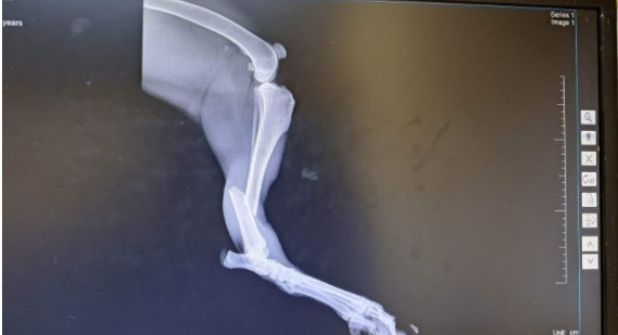

Aquejado por los dolores que tiene en su pata trasera, de la que resultó con múltiples fracturas, 'Max' necesita ser operado en las próximas horas o días, para salvar su extremidad, de lo contrario corre el riesgo de que la pierda.

En su pata necesitan colocarle una placa y varios tornillos, por lo que una vez que sea operado deberá permanecer bajo el cuidado del hospital en su recuperación, que será de aproximadamente un mes y medio.

Por ahora en la veterinaria donde está internado se le están suministrando medicamentos, pero también se debe de cubrir los pagos por concepto de consulta y rayos X.